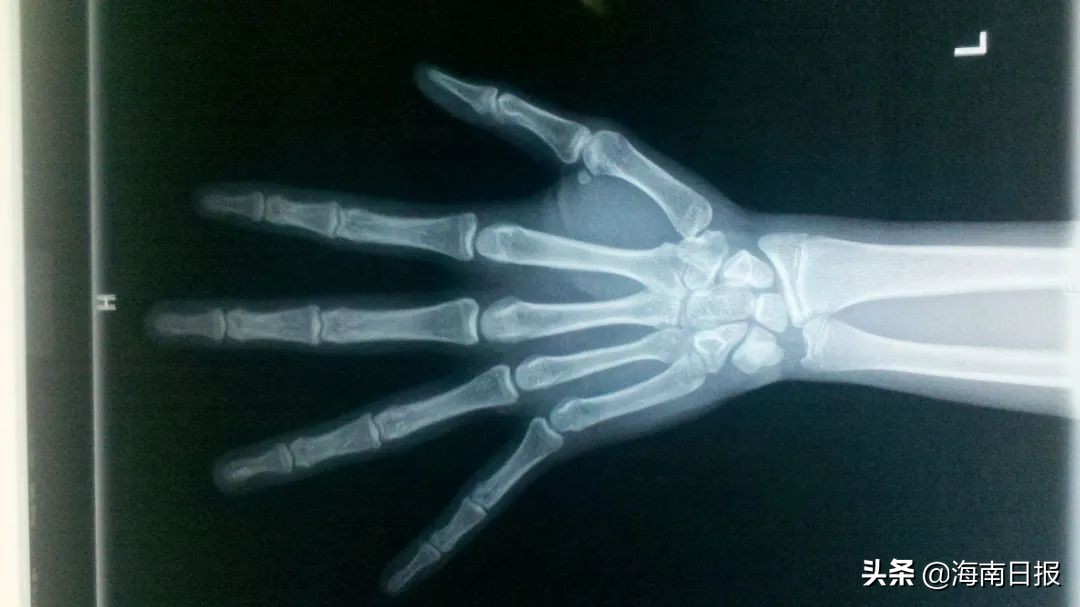

另外,还可以进行相关的检查,最基本的便是拍骨龄片。

很多家长认为骨龄片是个很高深的检查,其实很简单,就是拍一个左手的X光片,然后医生就可以判断孩子的生长潜力,并进行初步的身高预测。

其中,骨龄正常应该和实际年龄相差1岁以内,也就是说骨龄小于年龄1岁或大于年龄1岁都是正常的。

但如果相差1岁以上,便是不正常的情况需要查找原因。生活中常见的性早熟,骨龄就会明显超过实际年龄,从而导致生长潜力受损,引起成年后的矮小。